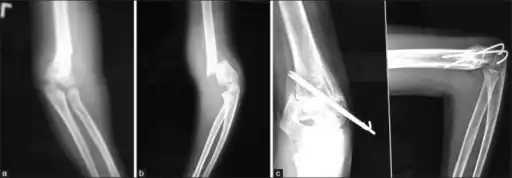

a) Pre-operative A-P radiograph b) pre-operative Lateral radiograph shows Supracondylar fracture of humerus c) post-operative A-P and Lateral radiographs of Supracondylar fracture of humerus showing with 2 lateral K-wire fixation

Treatment options for supracondyl humerus fractures vary depending if the bone is displaced (out of position) or not displaced (see classification section above).[1]